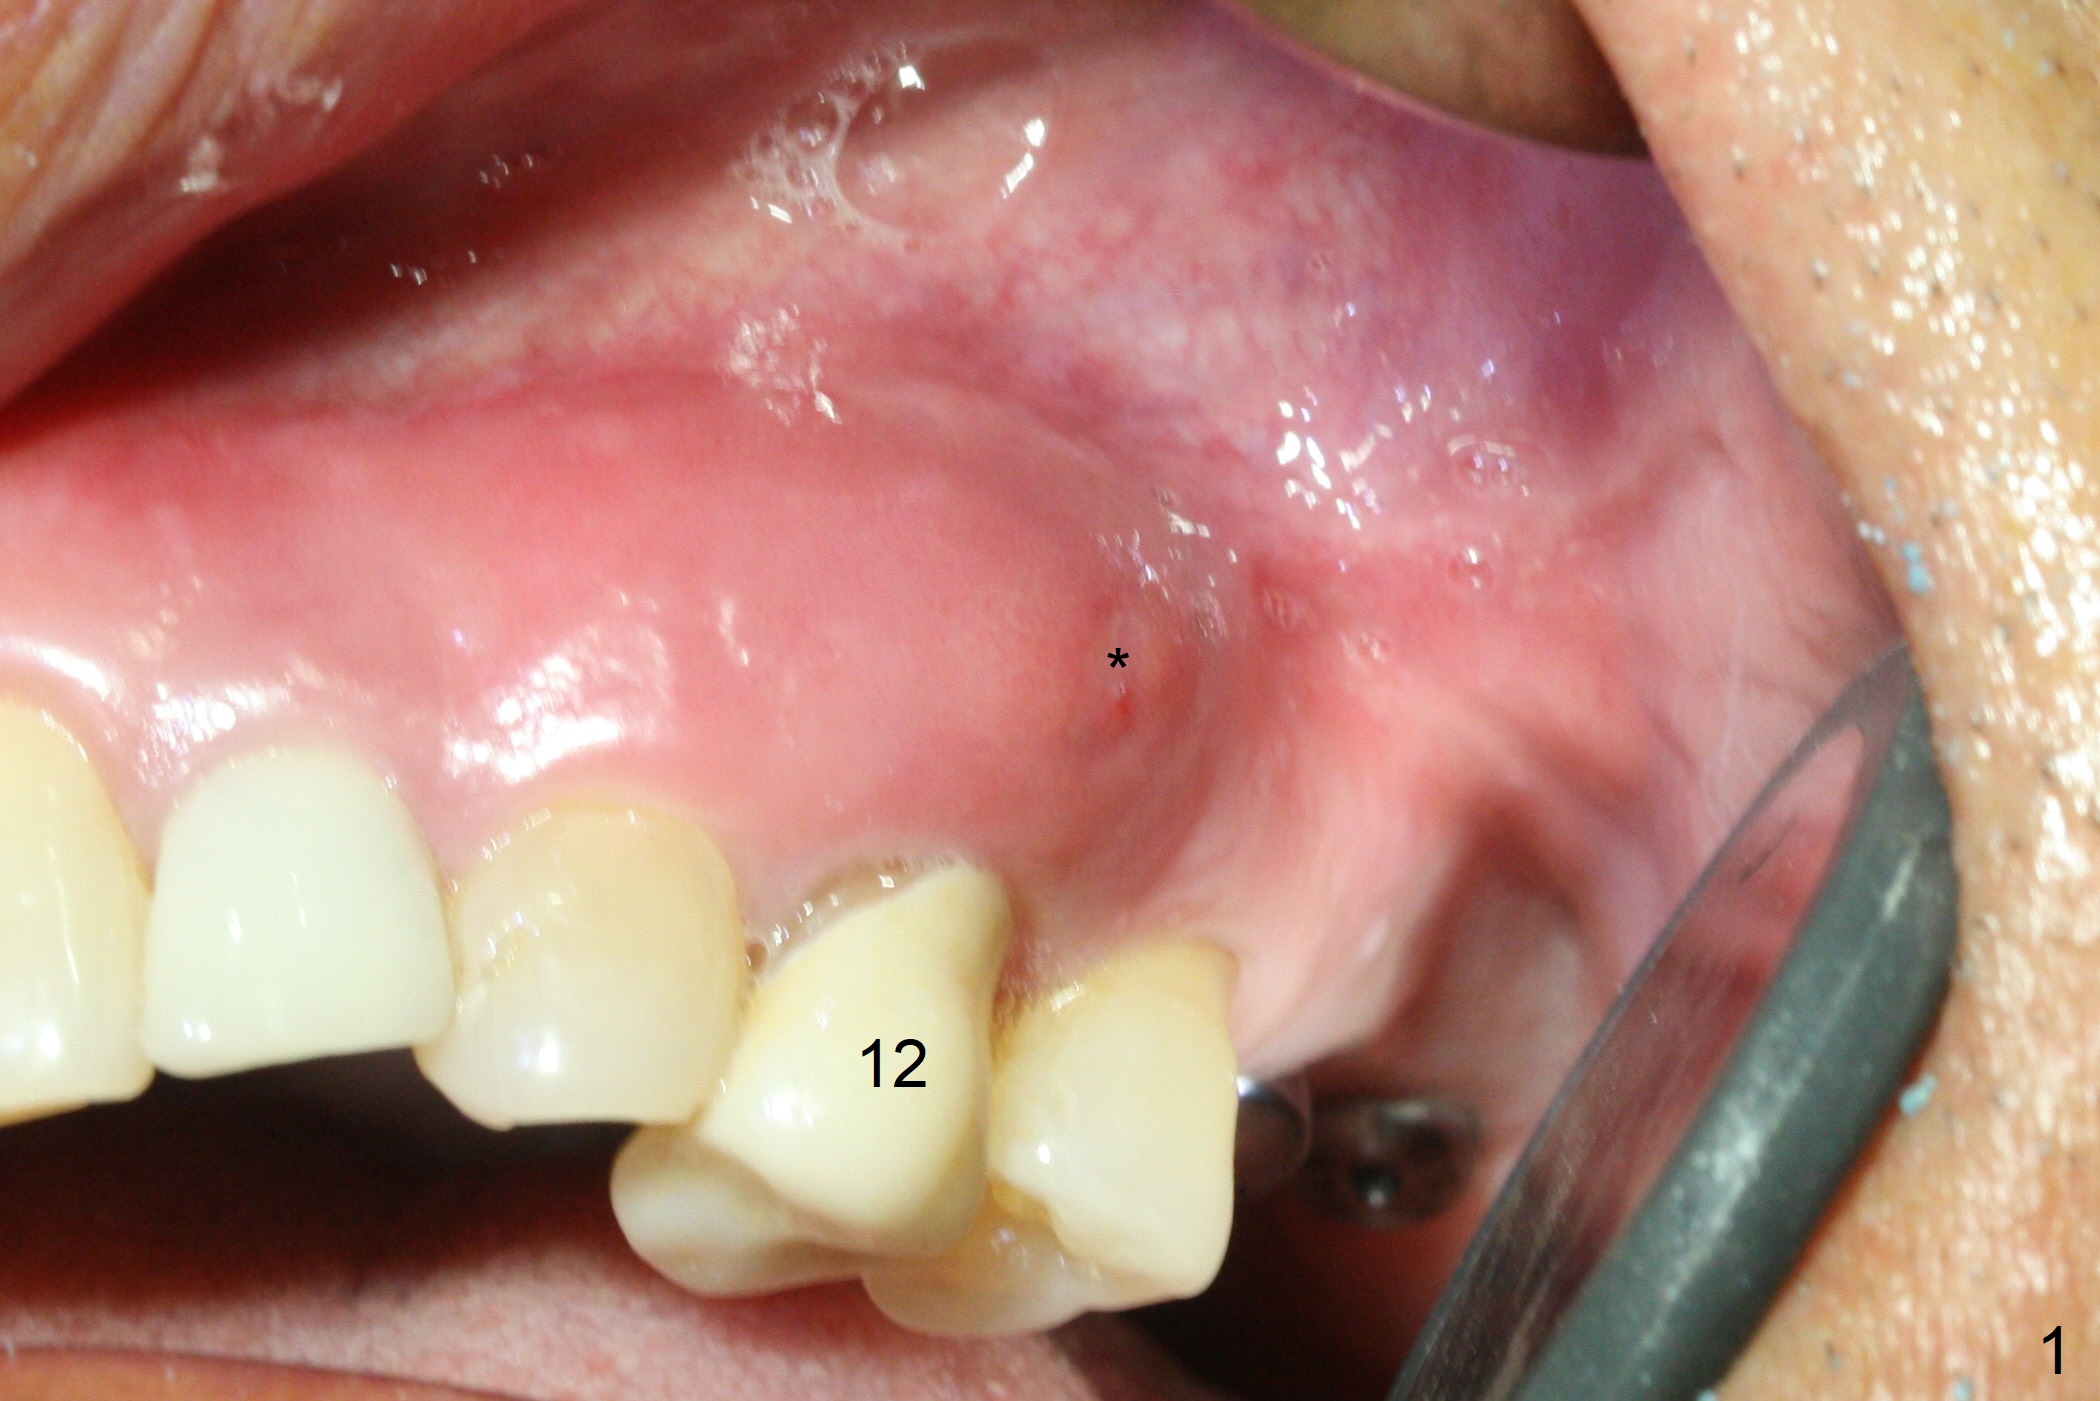

A few days prior to surgery, the tooth #12 developed abscess, self controlled by water pik (Fig.1 *). The buccal plate is defective. Initial osteotomy is close to the root of the tooth #11 (Fig.2). After adjustment of the trajectory and the depth of osteotomy (Fig.3), a 3.8x15 mm dummy implant is placed (Fig.4,5). In spite of a shorter implant (3.8x13 mm) placed deeper, approximately 7 mm implant threads are not covered buccally by the native bone (Fig.6 red dashed line). If the implant were placed deeper, the crown/implant ratio would become more unfavorable (abutment screw loosening, Fig.7). Since a mill abutment (4.5(2) mm) is inserted before Vanilla Graft, the deepest portion of the socket is unfilled (Fig.7 *). With meticulous use of a long explorer and additional allograft, the space is closed (Fig.8 *). The buccal plate collapses with apparently fistula formation 2 months postop. The patient removes the provisional for cleaning. It appears that the mill abutment is buccally placed and needs heavy reduction. The mill abutment is loose 2 months 10 days postop. When it is retightened, it tilts distal. Bone remains around the implant 6 months postop (Fig.9). Without a provisional at #12 for 5 months, the tooth #13 appears to have been shifted mesially (Fig.10 arrow). The mill abutment at #12 changes to a healing one. A lingual button is placed in the mesial surface of #13. Splinted provisional is fabricated with supraocclusion at #14 and 15 as an anchor (implants). The tooth #13 is being distalized with power chains. Limited ortho is finished nearly 2 months post banding (Fig.15,16).